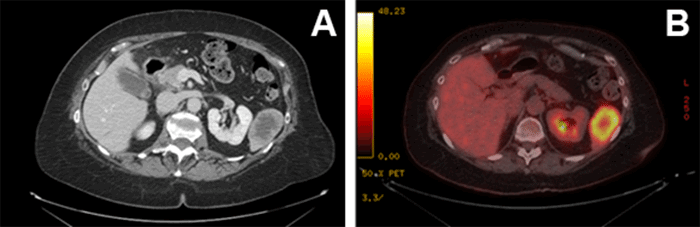

The patient is a 59-year-old female with a history of synchronous stage IV rectal cancer status post perioperative chemotherapy, neoadjuvant chemoradiotherapy, and low anterior resection, total abdominal hysterectomy with bilateral salpingo-oophorectomy, and partial hepatectomy. Five years post-resection, a surveillance computed tomography (CT) scan revealed interval development of a 5.8 cm × 3.5 cm hypodense lesion in the inferior pole of the spleen (Figure 1A). Positron emission tomography (PET) demonstrated fluorodeoxyglucose F-18 (FDG) avidity (Figure 1B). Her CEA levels remained within normal limits. Laparoscopic splenectomy was performed (Figure 2). Pathology revealed metastatic, moderately differentiated adenocarcinoma of colorectal primary (Figure 3).

Figure 1. Solitary Lesion in Inferior Pole of Spleen on CT (A) with FDG Avidity on PET (B). Published with Permission